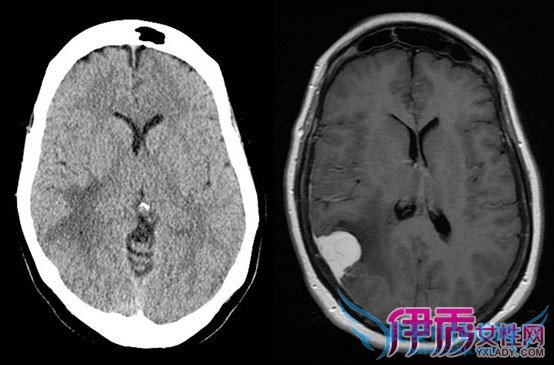

Í·ÂCTɨÃè

µäÐ͵ÄÄÔĤÁö£¬ÔÚδÔöÇ¿µÄCTɨÃèÖУ¬³ÊÏÖ¹ÂÁ¢µÄµÈÃܶȻò¸ßÃܶÈռλ²¡±ä¡£Æä»ùµ×½Ï¿í£¬ÃܶȾùÔÈÒ»Ö£¬±ßÔµÇåÎú£¬ÁöÄڿɼû¸Æ»¯¡£ÔöÇ¿ºó¿É¼ûÖ×ÁöÃ÷ÏÔÔöÇ¿£¬¿É¼ûÄÔĤβÕ÷¡£

´Å¹²ÕñɨÃè

¶ÔÓÚͬһ²¡ÈË£¬×îºÃͬʱ½øÐÐCTºÍMRIµÄ¶Ô±È·ÖÎö£¬·½¿ÉµÃµ½½ÏÕýÈ·µÄ¶¨ÐÔÕï¶Ï¡£